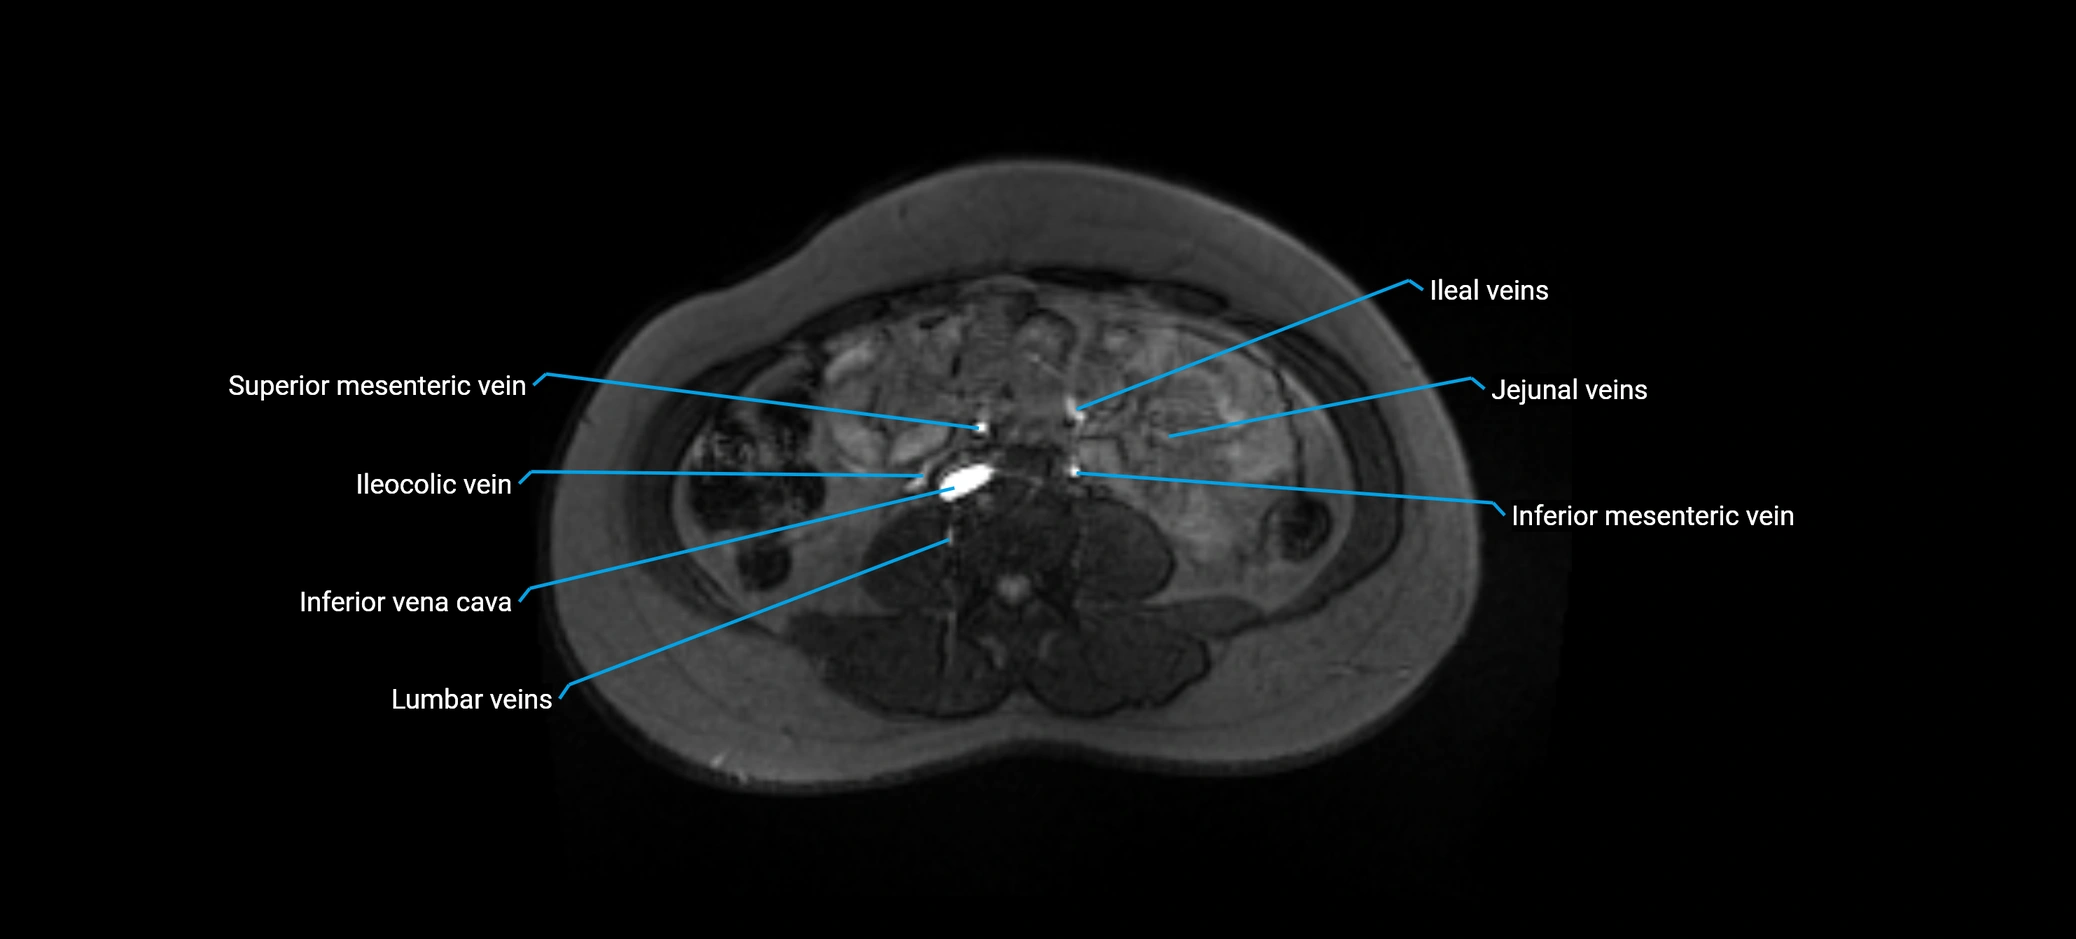

MRI image

image